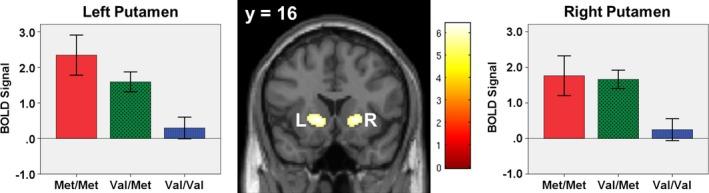

There was a significant main effect of genotype on brain activation in left and right putamen during successful versus failed inhibition and in right inferior frontal gyrus/insula during successful inhibition versus baseline. Follow-up tests revealed that Met homozygotes had greater activation in each region relative to Val homozygotes.

在成功抑制与失败抑制期间,基因型对左右壳核的脑激活有显著的主效应;在成功抑制与基线期相比时,基因型对右侧额下回/脑岛有显著主效应。后续测试显示,与缬氨酸纯合子相比,蛋氨酸纯合子在每个区域的激活程度更高。